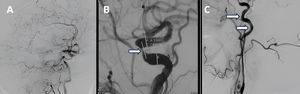

Adicionalmente, dada la intención de realizar la remoción de la carga trombótica, se solicitó una panangiografía cerebral (fig. 1), en la que se evidenció un eje carotídeo derecho ocluido crónicamente por enfermedad ateroesclerótica, mientras que el eje izquierdo presentó una estenosis crítica del sifón carotídeo con presencia de trombos móviles agudos a nivel de la arteria carótida interna izquierda.

Panangiografía cerebral. A)Vista sagital de la panangiografía cerebral con presencia de ateromatosis generalizada. B)La flecha indica la presencia de ateromatosis y estenosis crítica a nivel del sifón carotídeo izquierdo. C)Las flechas indican la presencia de defectos de llenado debido a la presencia de algunos trombos móviles a nivel de la carótida interna izquierda.